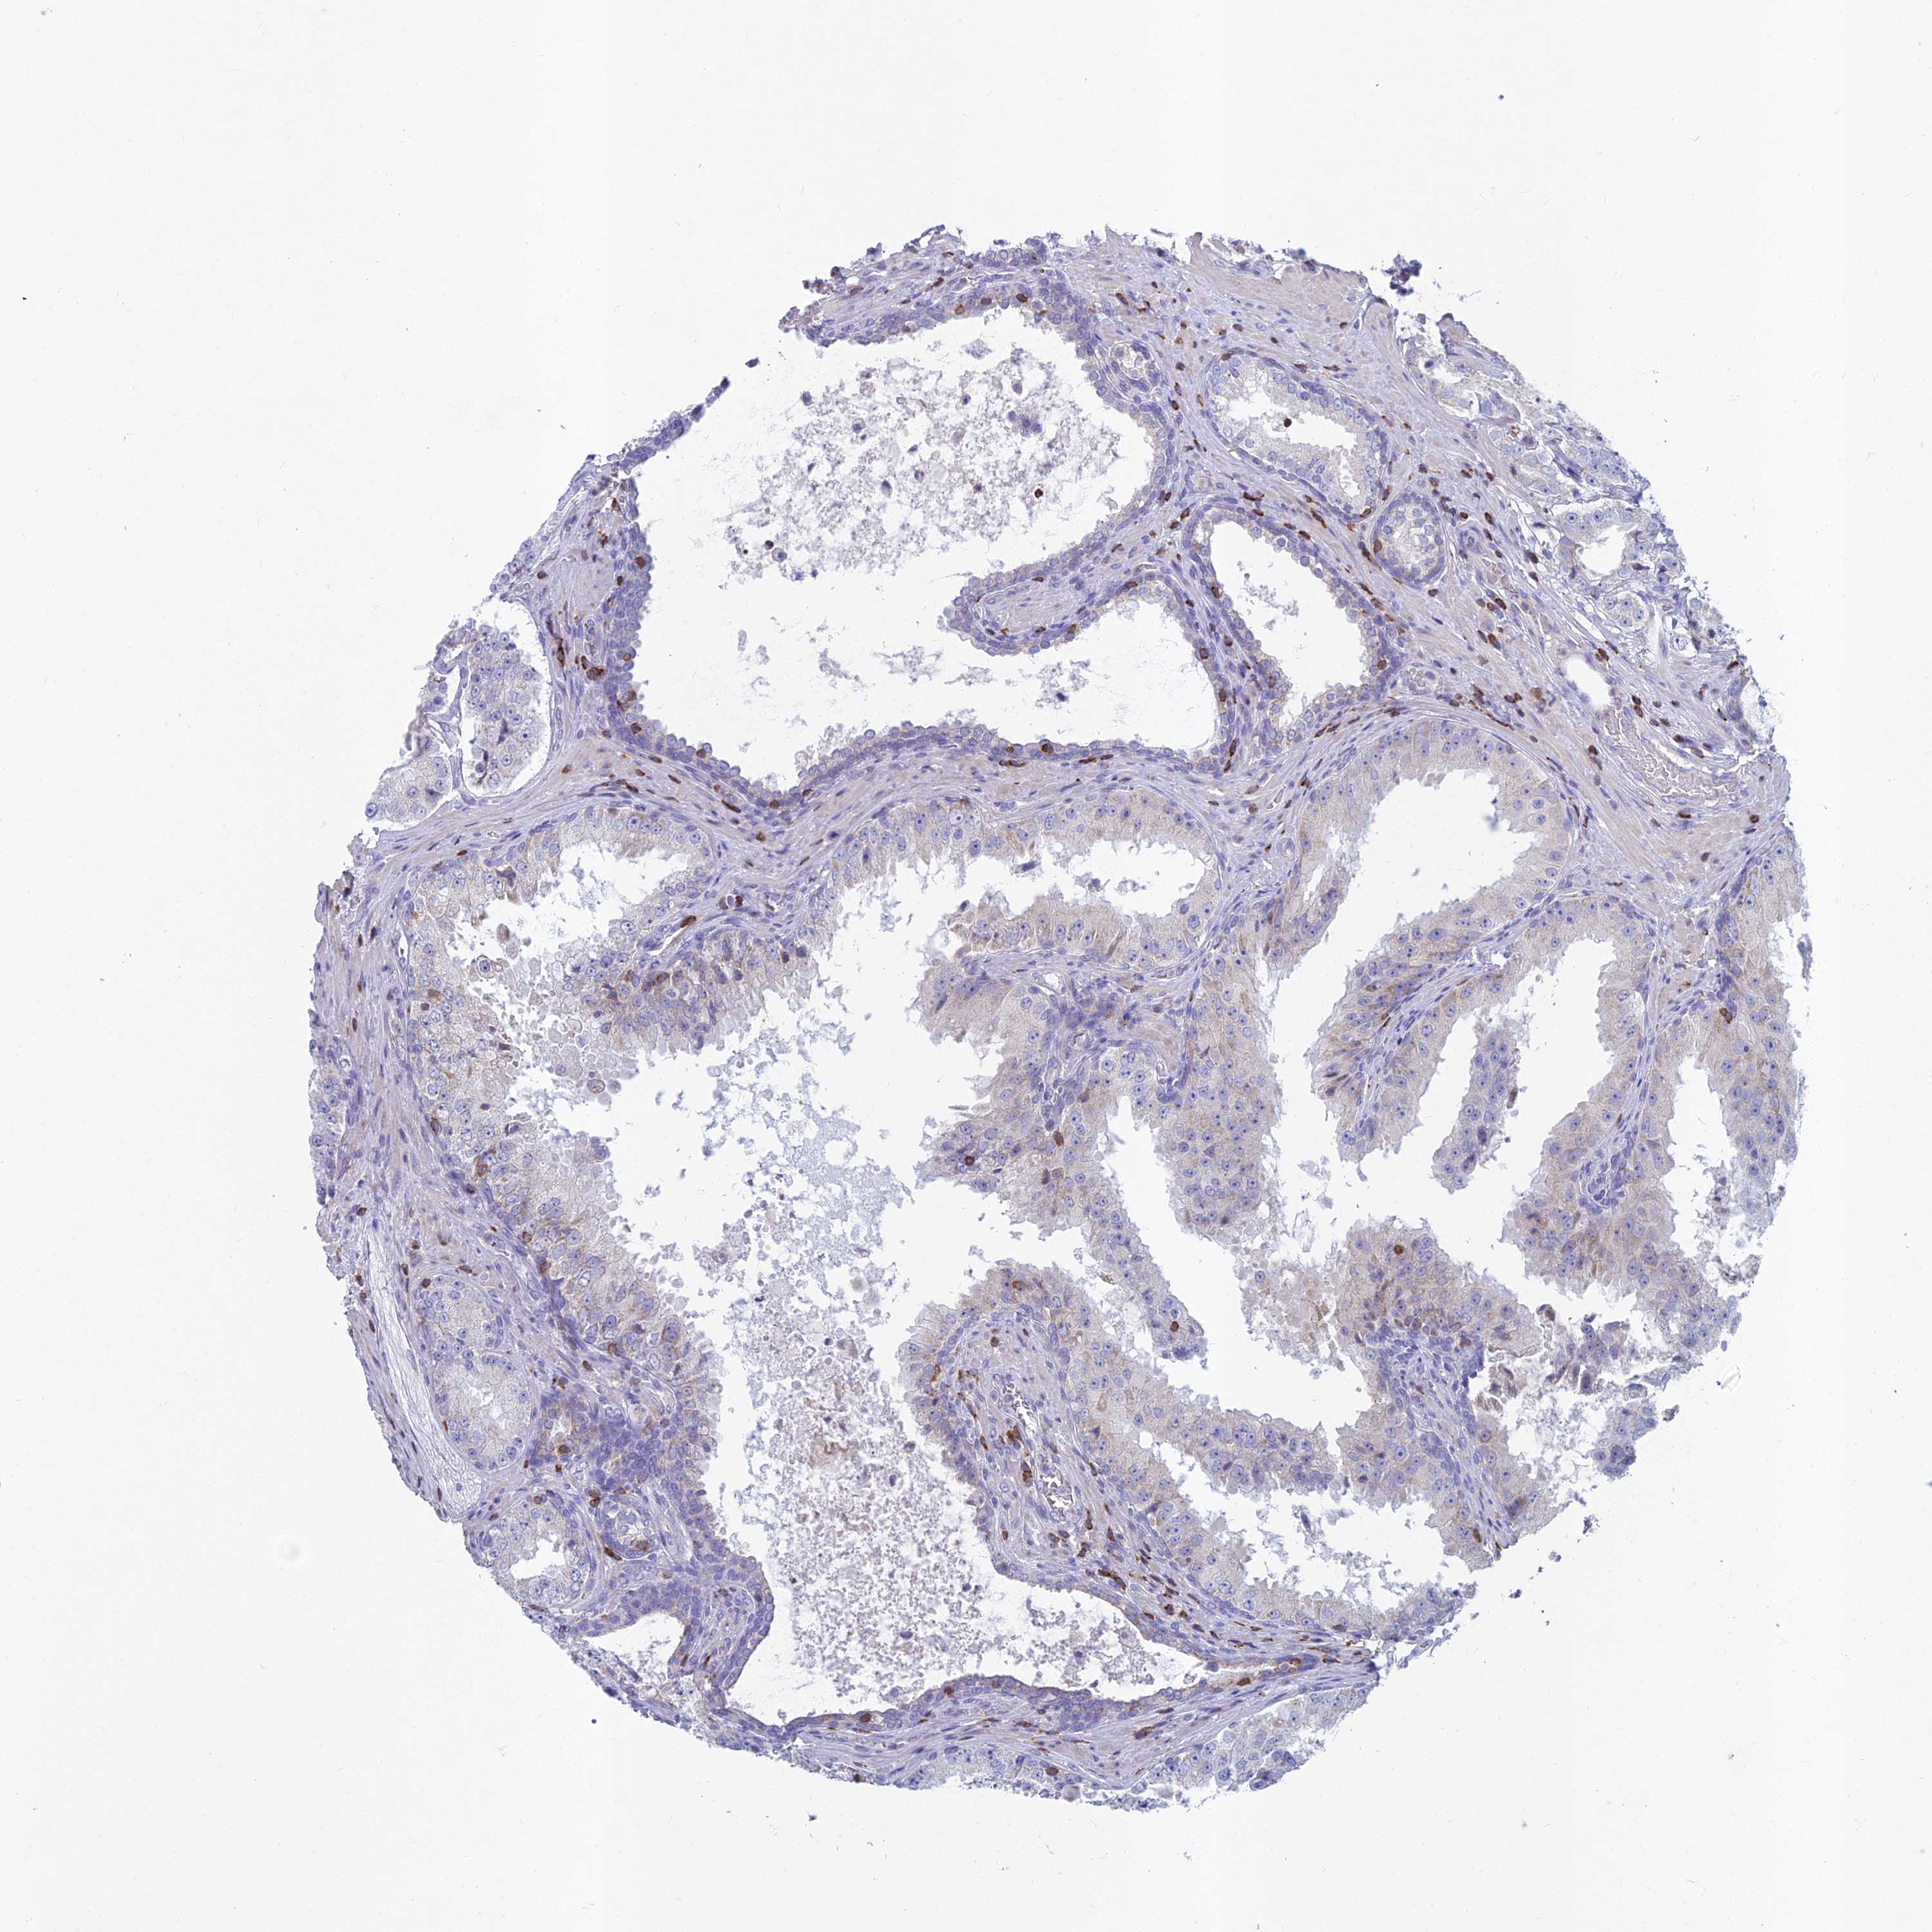

PROSTATE CANCER - Protein expressioni

A mouse-over function shows sample information and annotation data. Click on an image to view it in a full screen mode. Samples can be filtered based on level of antibody staining by selecting one or several of the following categories: high, medium, low and not detected. The assay and annotation is described here.

Note that samples used for immunohistochemistry by the Human Protein Atlas do not correspond to samples in the TCGA dataset.

Antibody stainingi

Antibody staining in the annotated cell types in the current human tissue is reported as not detected, low, medium, or high, based on conventional immunohistochemistry profiling in selected tissues. This score is based on the combination of the staining intensity and fraction of stained cells.

Each image is clickable and will lead to virtual microscopy that enables deeper exploration of all samples and also displays staining intensity scores, fraction scores and subcellular localization as well as patient and tissue information for each sample.

Antibody HPA044127

Staining

High

Medium

Low

Not detected

Intensity

Strong

Moderate

Weak

Negative

Quantity

>75%

75%-25%

<25%

None

Location

Nuclear

Cytoplasmic/membranous

Cytoplasmic/membranous,nuclear

Adenocarcinoma, High grade

Adenocarcinoma, Low grade